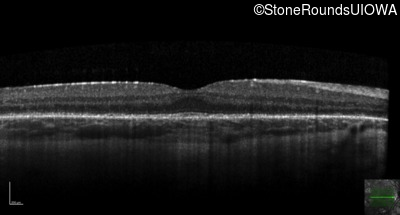

Optical Coherence Tomography - Right - 20/32

Exemplar / OCT Stack